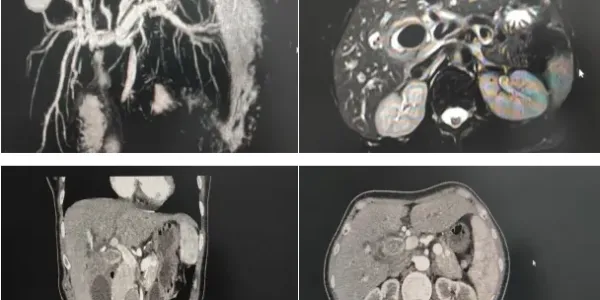

56岁女性患者,“梗阻性黄疸”收住普外科,患者入院后,经过腹部增强CT及MRCP检查显示:胆囊结石嵌顿伴胆囊炎,压迫邻近肝门部胆管致以上肝内外胆管扩张伴胆管炎,Mirizzi综合征需要手术治疗。

术前核磁及增强CT片